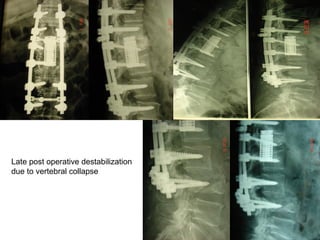

Late post operative destabilization

due to vertebral collapse

Lumbar – Sacral –Iliac

stabilization and

Interbody cages